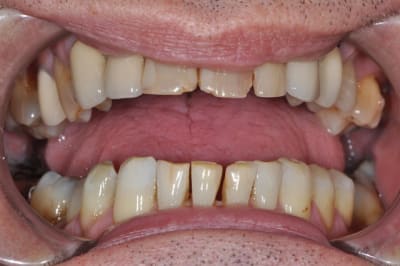

Pas mal les photos mais on pourrait avoir des vrais photos de sourire pour comprendre comment le patient se voit.

la réalisation d'un traitement global prothétique ou d'ortho se tient au regard de l'affaissement occlusal du bloc postérieur, l'occlusion plus ou moins foireuse de ton patient risque de le placer devant un pronostic esthétique moyen à long terme, c'est déja le cas au niveau 23 et 24, donc se contenter de 12 à 22 me parait léger. Mais bon le terme esthétique est tellement floue!

pour danteyeah,

le patient sourit ainsi,

il est complexé par ses dents de devant depuis de nombreuses années ( il a 58 ans )

son souhait n'est pas d'avoir la bouche parfaite mais de pouvoir sourire.

OK on y voit plus clair, si on prend l'image comme une référence, ce qui me choc autant que le bloc antérieur d'un point de vue esthétique (et là encore c'est une vision subjective donc à faire valider au patient d'abord), c'est la position de 14, 15 ,16, ingressées suite à affaissement occlusal, oui je sais c'est fonctionnel, mais c'est moche aussi!!!!

Ensuite sérieusement les CCM en place font toc, c'est aussi moche, encore une fois ce contenter de 12 à 22 me semble léger, même si dans le shèma du sourire "vrai" l'esthétique de la gencive est tout d'un coup devenue secondaire.

Alors ce battre pour savoir si on fait des couronnes ceramoceram ou des 3/4 ou des facettes, alors que le reste ne ressemble à rien, n'a plus trop de sens non?